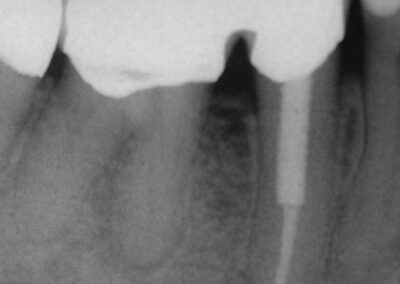

Und zum Abschluss noch eine schöne Doublette:

Galerie: